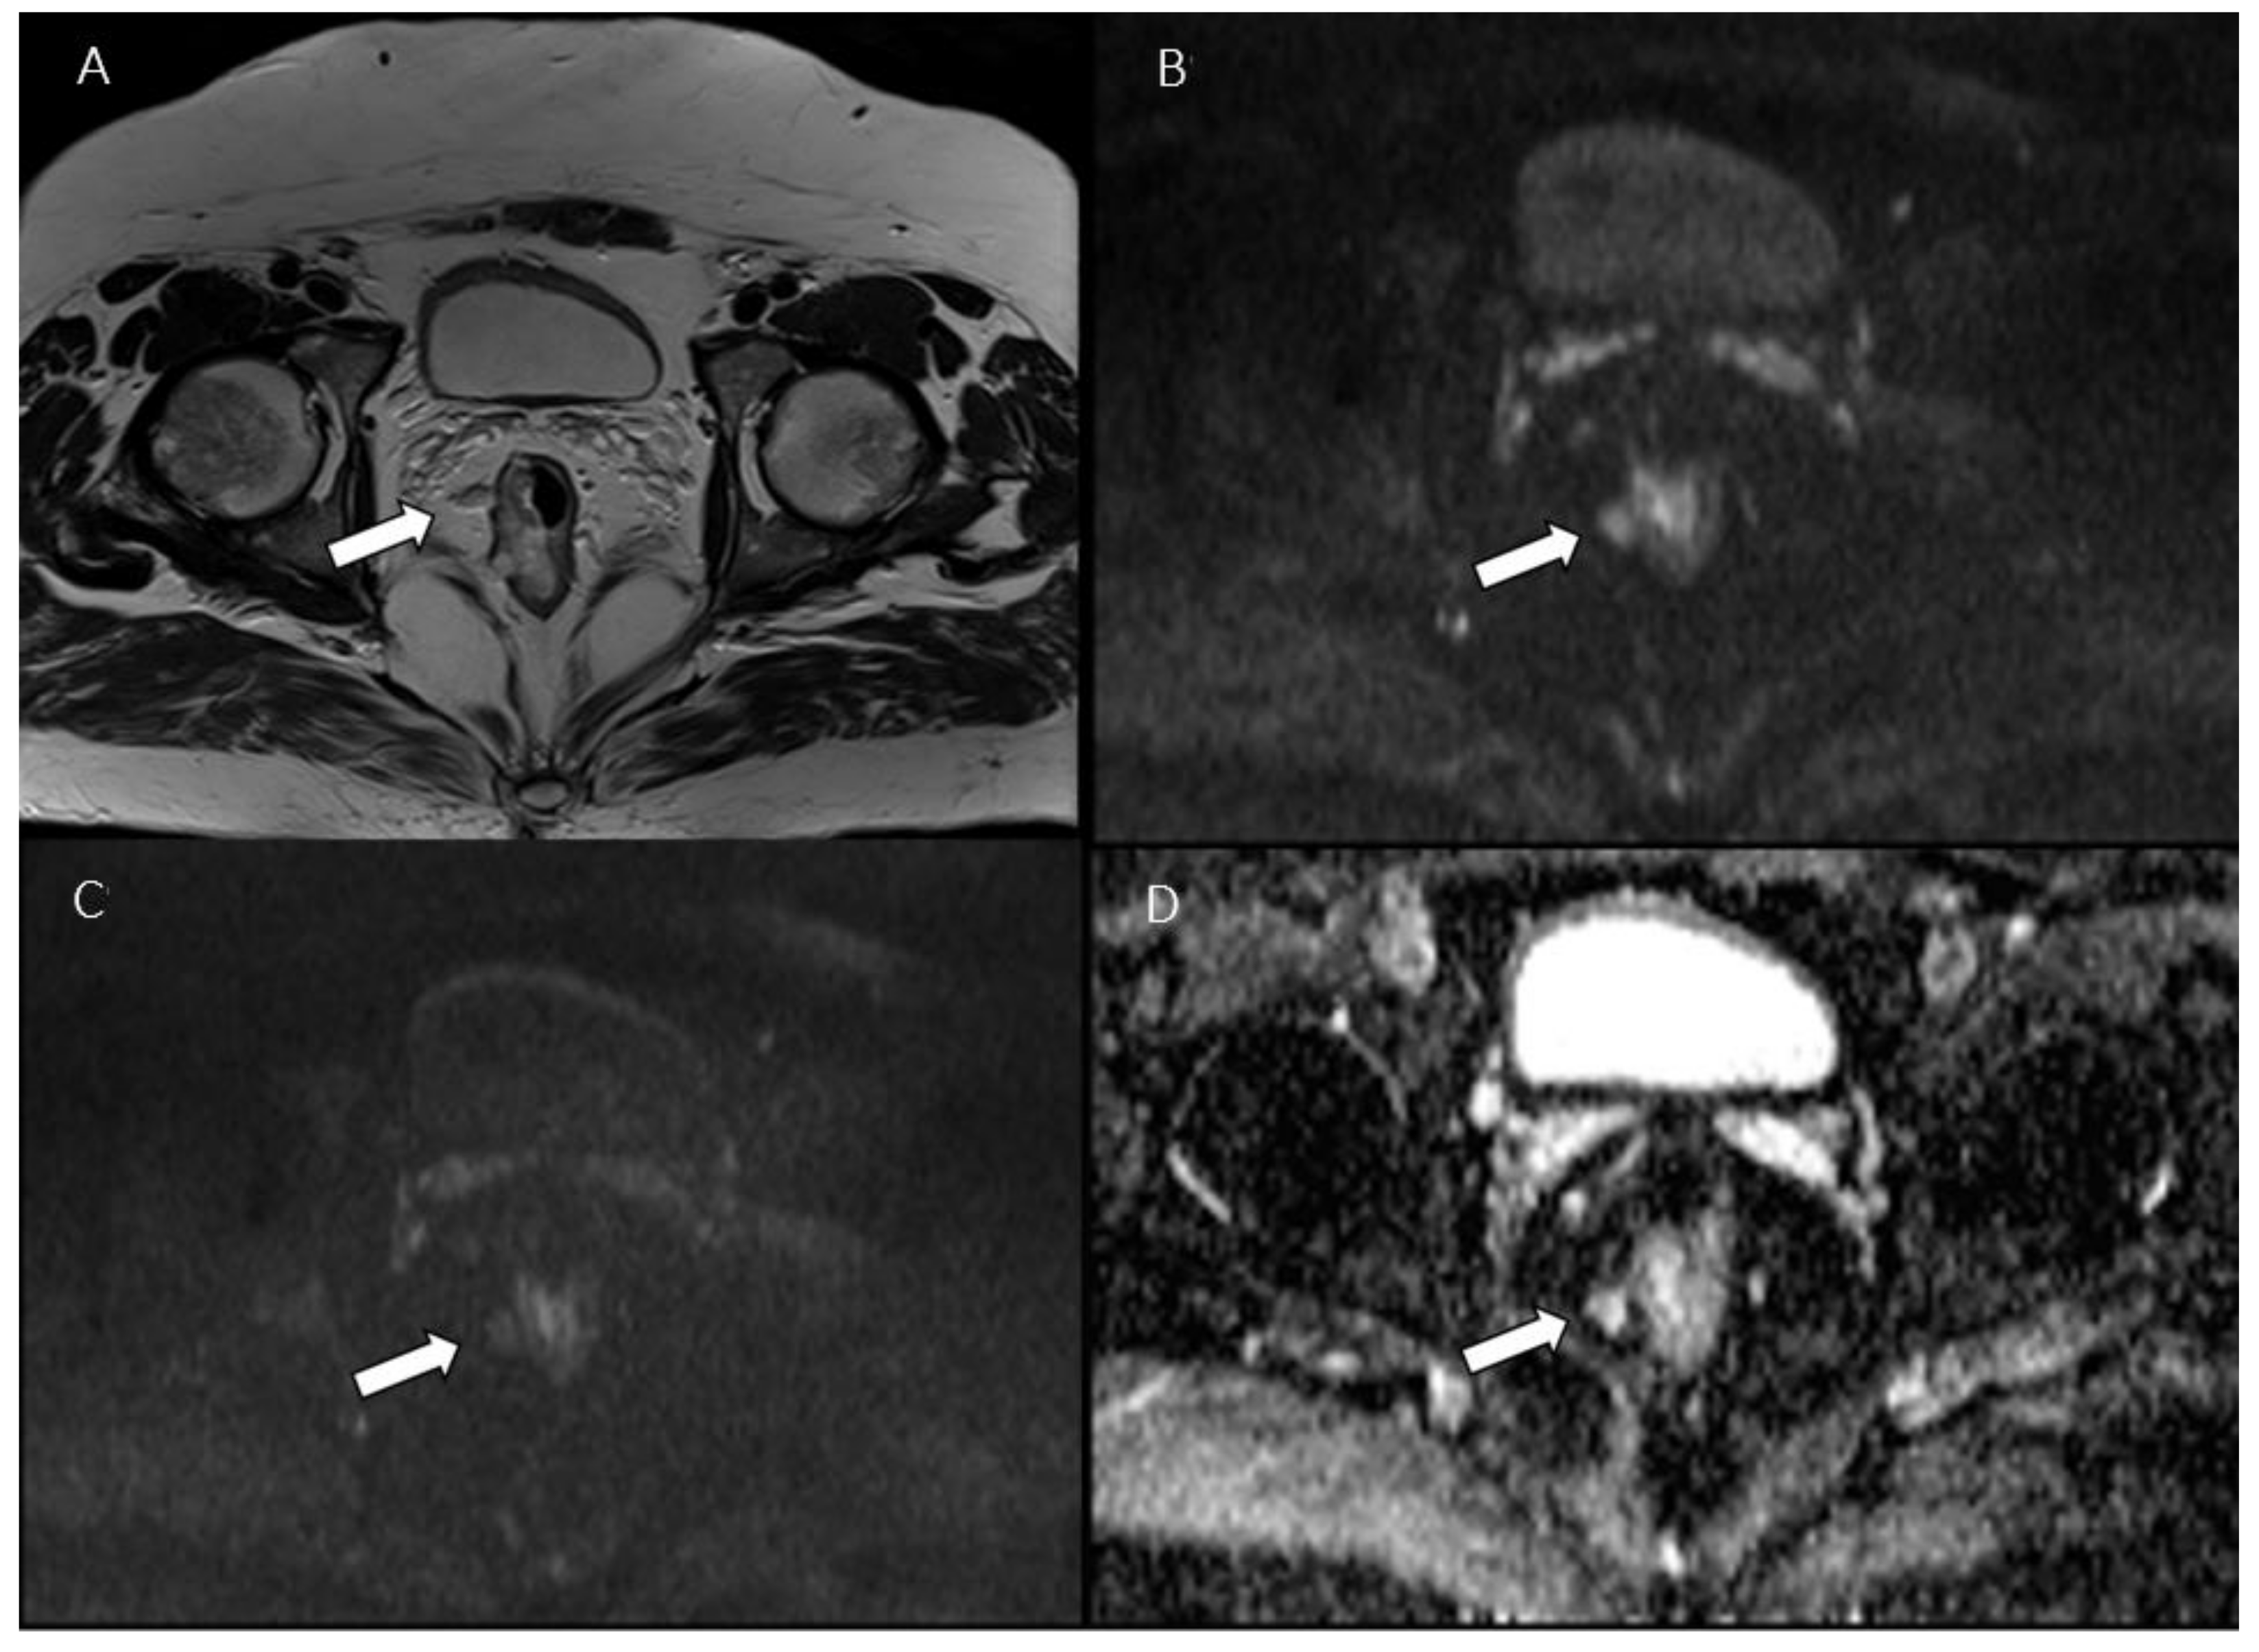

- Yu, X.; Wen, L.; Hou, J.; Bi, F.; Hu, P.; Wang, H.; Wang, W. Discrimination between Metastatic and Nonmetastatic Mesorectal Lymph Nodes in Rectal Cancer Using Intravoxel Incoherent Motion Diffusion-Weighted Magnetic Resonance Imaging. Acad. Radiol. 2016, 23, 479–485. [Google Scholar] [CrossRef] [PubMed]

- Qiu, L.; Liu, X.; Liu, S.; Weng, Z.; Chen, X.; Feng, Y.; Cai, X.; Guo, C. Role of Quantitative Intravoxel Incoherent Motion Parameters in the Preoperative Diagnosis of Nodal Metastasis in Patients with Rectal Carcinoma. J. Magn. Reson. Imaging 2016, 44, 1031–1039. [Google Scholar] [CrossRef]

- Long, L.; Zhang, H.; He, X.; Zhou, J.; Guo, D.; Liu, X. Value of Intravoxel Incoherent Motion Magnetic Resonance Imaging for Differentiating Metastatic from Nonmetastatic Mesorectal Lymph Nodes with Different Short-Axis Diameters in Rectal Cancer. J. Cancer Res. Ther. 2019, 15, 1508. [Google Scholar] [CrossRef]